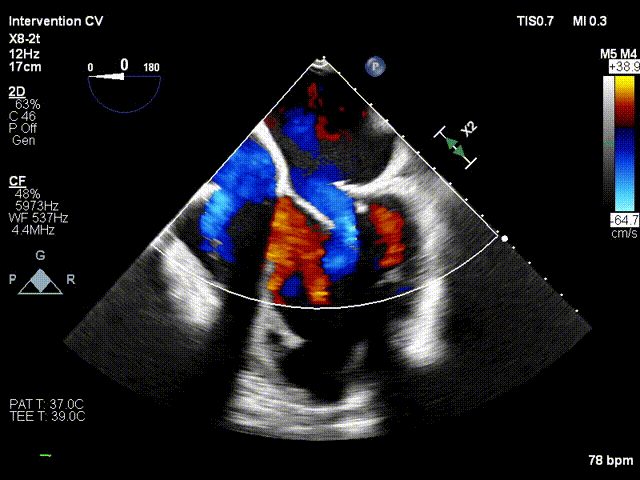

TMVR术后

术后第2天患者出监护室,术后第4天拔管,术后第5天顺利出院。出院前心超显示:经导管二尖瓣人工瓣膜植入术后,人工瓣膜支架固定,形态未见异常,瓣叶开放不受限,瓣口由多普勒估测其开放峰值流速为1.15m/s,峰值压差5mmHg,平均跨瓣压差为2mmHg,由连续多普勒据PHT估测面积约2.93cm²,瓣叶关闭形态未见异常,彩色多普勒未测及二尖瓣反流及瓣周漏;左心室流出道通畅,流出道峰值流速0.93m/s。

出院时Neo-LVOT